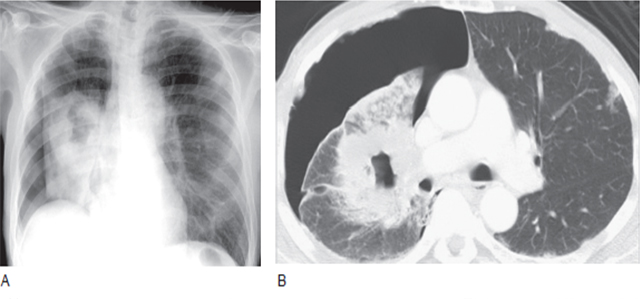

六、胸膜异常

1、气胸

在支气管肺癌中,自发性气胸很少见,常由脏层胸膜或胸膜腔直接侵犯导致(图19)。

图19 胸片和CT 上显示空洞型的鳞状细胞癌伴气胸